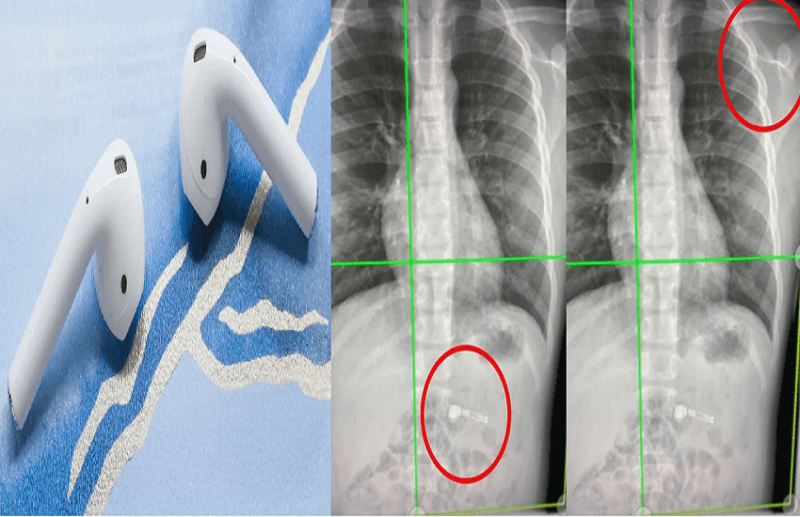

दरअसल, अमेरिका ( America ) के जॉर्जिया में एक माता-पिता ने अपने बच्चे को क्रिसमस का तोहफा दिया। इसमें उन्होंने अपने 7 साल के बच्चे को 2 Airpods गिफ्ट में दिए थे। बच्चे को ये गिफ्ट समज नहीं आया और उसने उन्हें मुंह में डाल लिया और निगल गया। ऐसे में Airpods पेट के अंदर चले गए। वहीं पैरेंट्स अपने बच्चे को लेकर तुरंत अस्पताल गए। डॉक्टर्स ने बच्चे का एक्स-रे किया, जिसे देखकर वो हैरान रह गए।

एक्स-रे में नजर आया कि दोनों Airpods बच्चे के पेट के अंदर थे। वहीं डॉक्टर्स ने कहा ये Airpods अपने आप नेचुरल प्रोसेस द्वारा पेट से बाहर निकल जाएंगे। वहीं मां कियारा ने बताया कि उनका बेटा बड़ा ही शरारती है। शरारत में ही वो इन्हें निगल गया। वहीं डॉक्टर्स ने बच्चे की जांच की और उसे दवाइयां भी दी। हालांकि, अब बच्चा ठीक है। लेकिन इस घटना ने माता-पिता की चिंता बढ़ा दी है क्योंकि बच्चे नाजाने मुंह में कब क्या डाल दें।